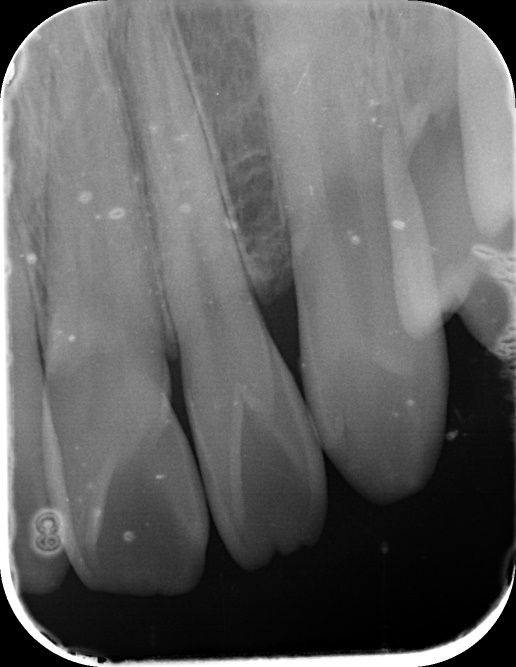

안녕하세요! 최근에 건강보험검진을 받으러가서 앞니 사이에 충치가 의심된다구 찍은 사진입니다.

1. 앞니에 충치가 있는건가요? (앞니 12, 11, 21, 22번 사이가 의심된다구 하셨습니다.)

• 1번 째 사진

엑스레이 사진상으로 보면 치아 사이에 작은 충치가 잇는것처럼 보이긴합니다. #11 12 사이 21 22사이는 사진상으로 보이는데 #11 21 사이는 사진상에 겹쳐보여 직접봐야 알수 잇을것같습니다.